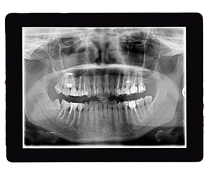

Digital X-Rays

Digital X-rays are an essential part of preventive and diagnostic dentistry, allowing us to detect issues early and monitor your oral health over time.

Compared to traditional X-rays, digital imaging uses significantly less radiation while producing clearer, more detailed images. These high-resolution images help us identify concerns such as cavities, infections, bone loss, and changes beneath the surface of the teeth and gums.

One of the biggest advantages is immediacy. Your images are available within seconds, which means we can review them with you chairside, explain what we’re seeing, and walk you through your options in real time.

This transparency helps you better understand your oral health and feel more involved in your treatment decisions. Early detection also means more conservative treatment whenever possible—helping preserve your natural teeth and avoid more complex procedures down the line.